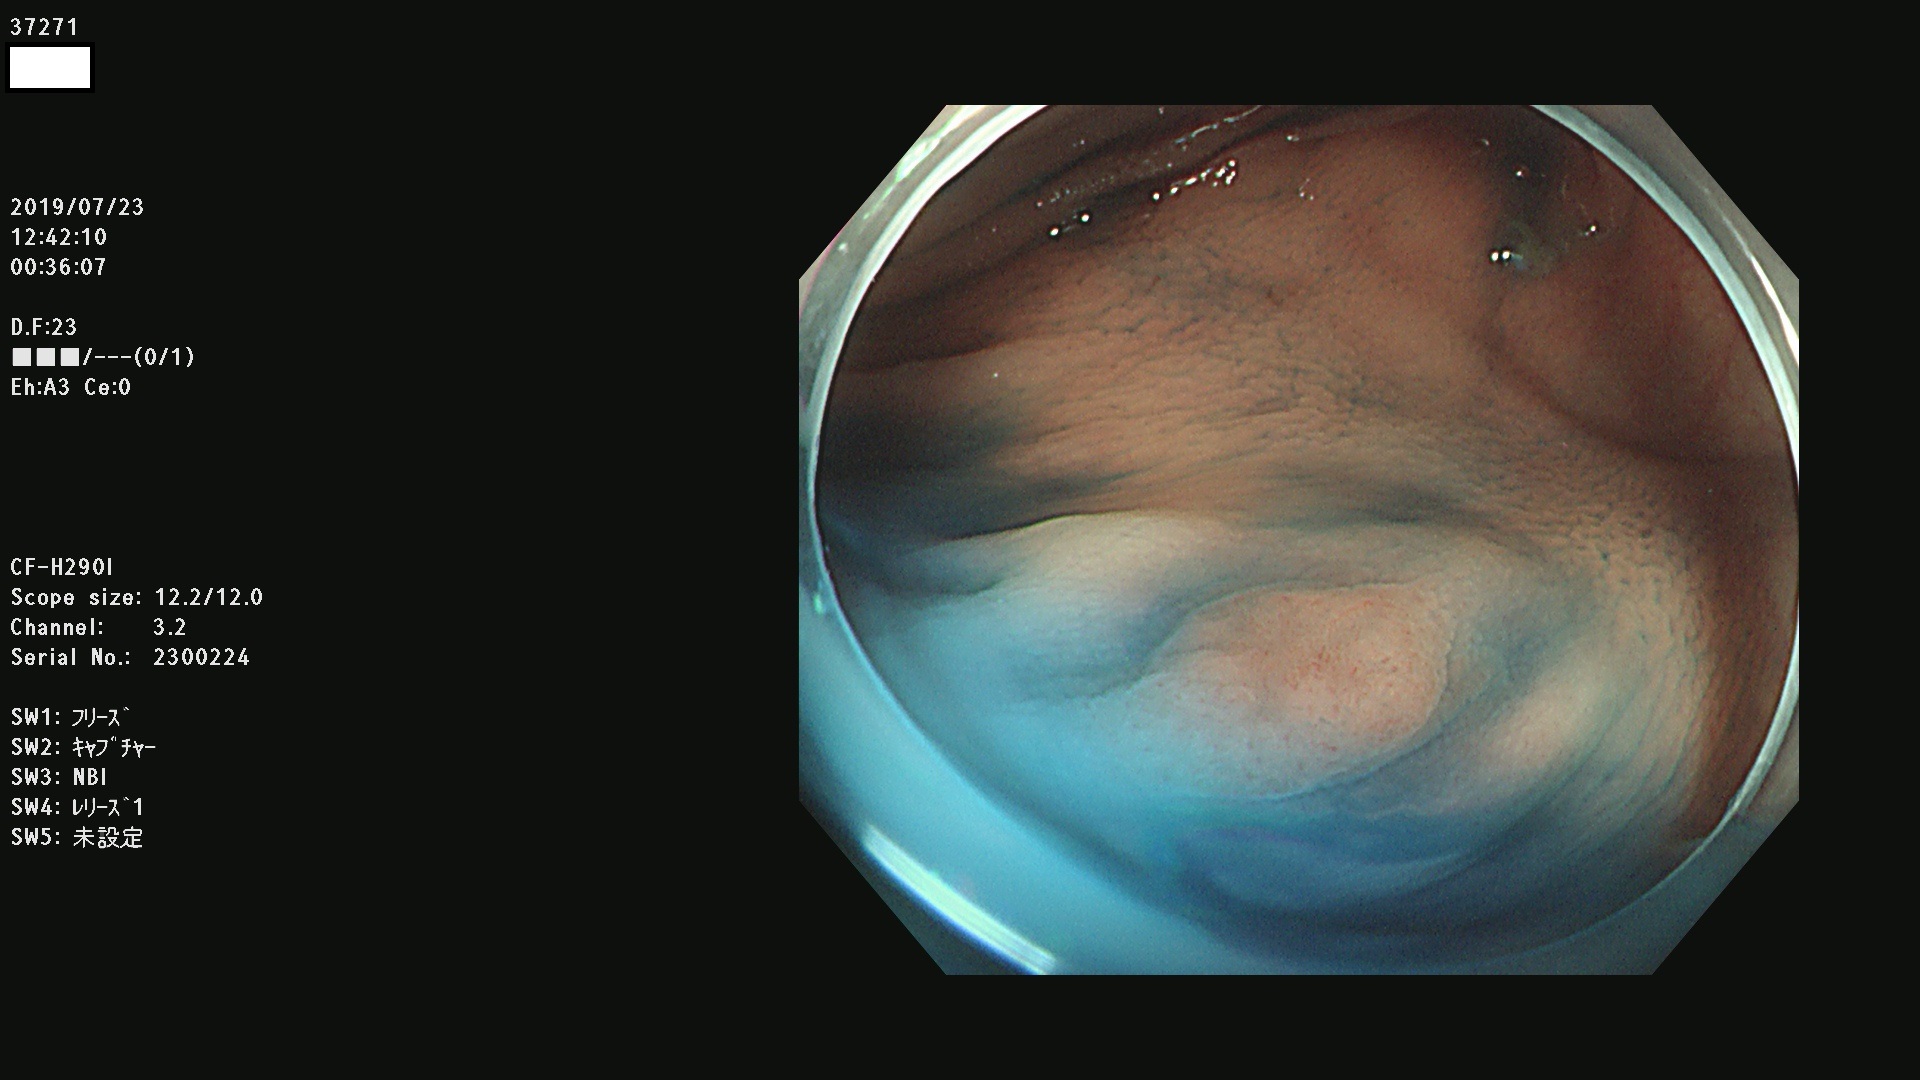

37200 37203 37204 37207 37208 37209 37210 37211 37212 37213 37214 37215 37216 37217 37220 37221 37222 37224 37225 37228 37229 37230 37232 37233 37234 37235 37236 37238 37241 37242 37243 37244 37245(SSAPのみ) 37247 37249 37250 37251 37252(SSAPのみ) 37254 37256 37257 37258 37259 37260(SSAPのみ) 37261(SSAPのみ) 37262 37263 37264 37265 37266 37267 37268(SSAPのみ) 37269 37271 37273 37274 37276 37277 37278 37279 37280 37281 37282 37284(SSAPのみ) 37285 37286 37288 37289 37290 37292 37293 37295 37296 37297(SSAPのみ)

発見困難で危険性の高い平坦型病変(上記100名より抽出)